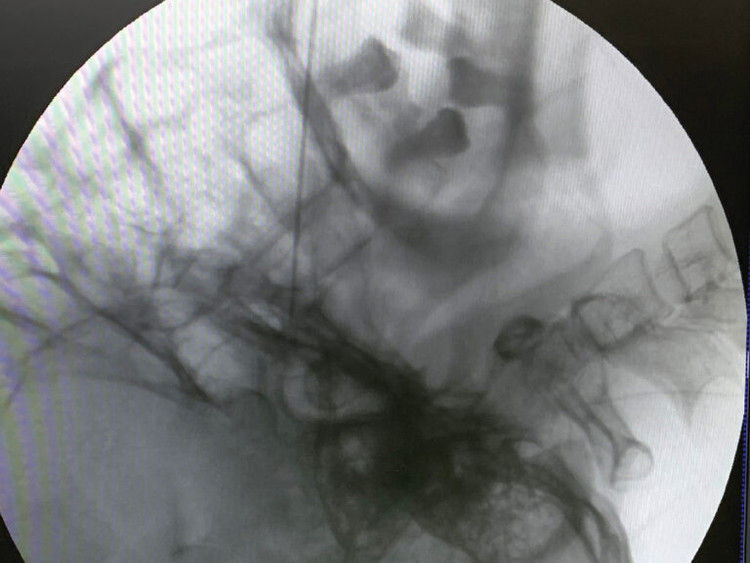

![]() |

| TS.BS Vi Trường Sơn – Trưởng khoa Ngoại yêu cầu thực hiện đốt sóng cao tần xung điều trị cho người bệnh - Ảnh BVCC |